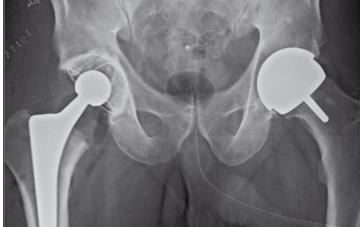

Fråga 2011-8 5p

Under året har man dragit tillbaka en av de mest använda s.k. ytersättningsproteser i höft från marknaden pga dåliga resultat.

A: Vilken typ av ledytor är det i denna protes?

B: Nämn 2 andra typer av ledytekombinationer som är vanliga i höftproteser

C. Diskutera fördelar och nackdelar med respektive ledytekombinationer

Svar: a) I en ytersättningsprotes är båda ledytorna av metall.

Fördelen är att det blir mycket lite slitage partiklar av en sådan led, förutsatt att protesen är insatt på rätt sätt. Man kan också göra ledskålen tunn eftersom metallen har hög hållfasthet.

Nackdelen är att om man sätter in protesen med fel vinklar får man en hög kantbelastning och högt slitage. Detta kan leda till mycket höga metallhalter i blodet och höga halter melallpartiklar runt protesen. Detta kan leda till utvecklande av pseudotumör.

b) Metall mot plast. Väl beprövat och med bra långtidsresultat. Ger på sikt ett plastslitage

som kan leda till osteolys. Detta kan man lösa genom att använda högt korsbunden plast som ger mindre slitage. Keramik mot keramik. Ger väldigt lite slitage. Kan dock ge upphov till gnisslande led och också keramikfraktur.